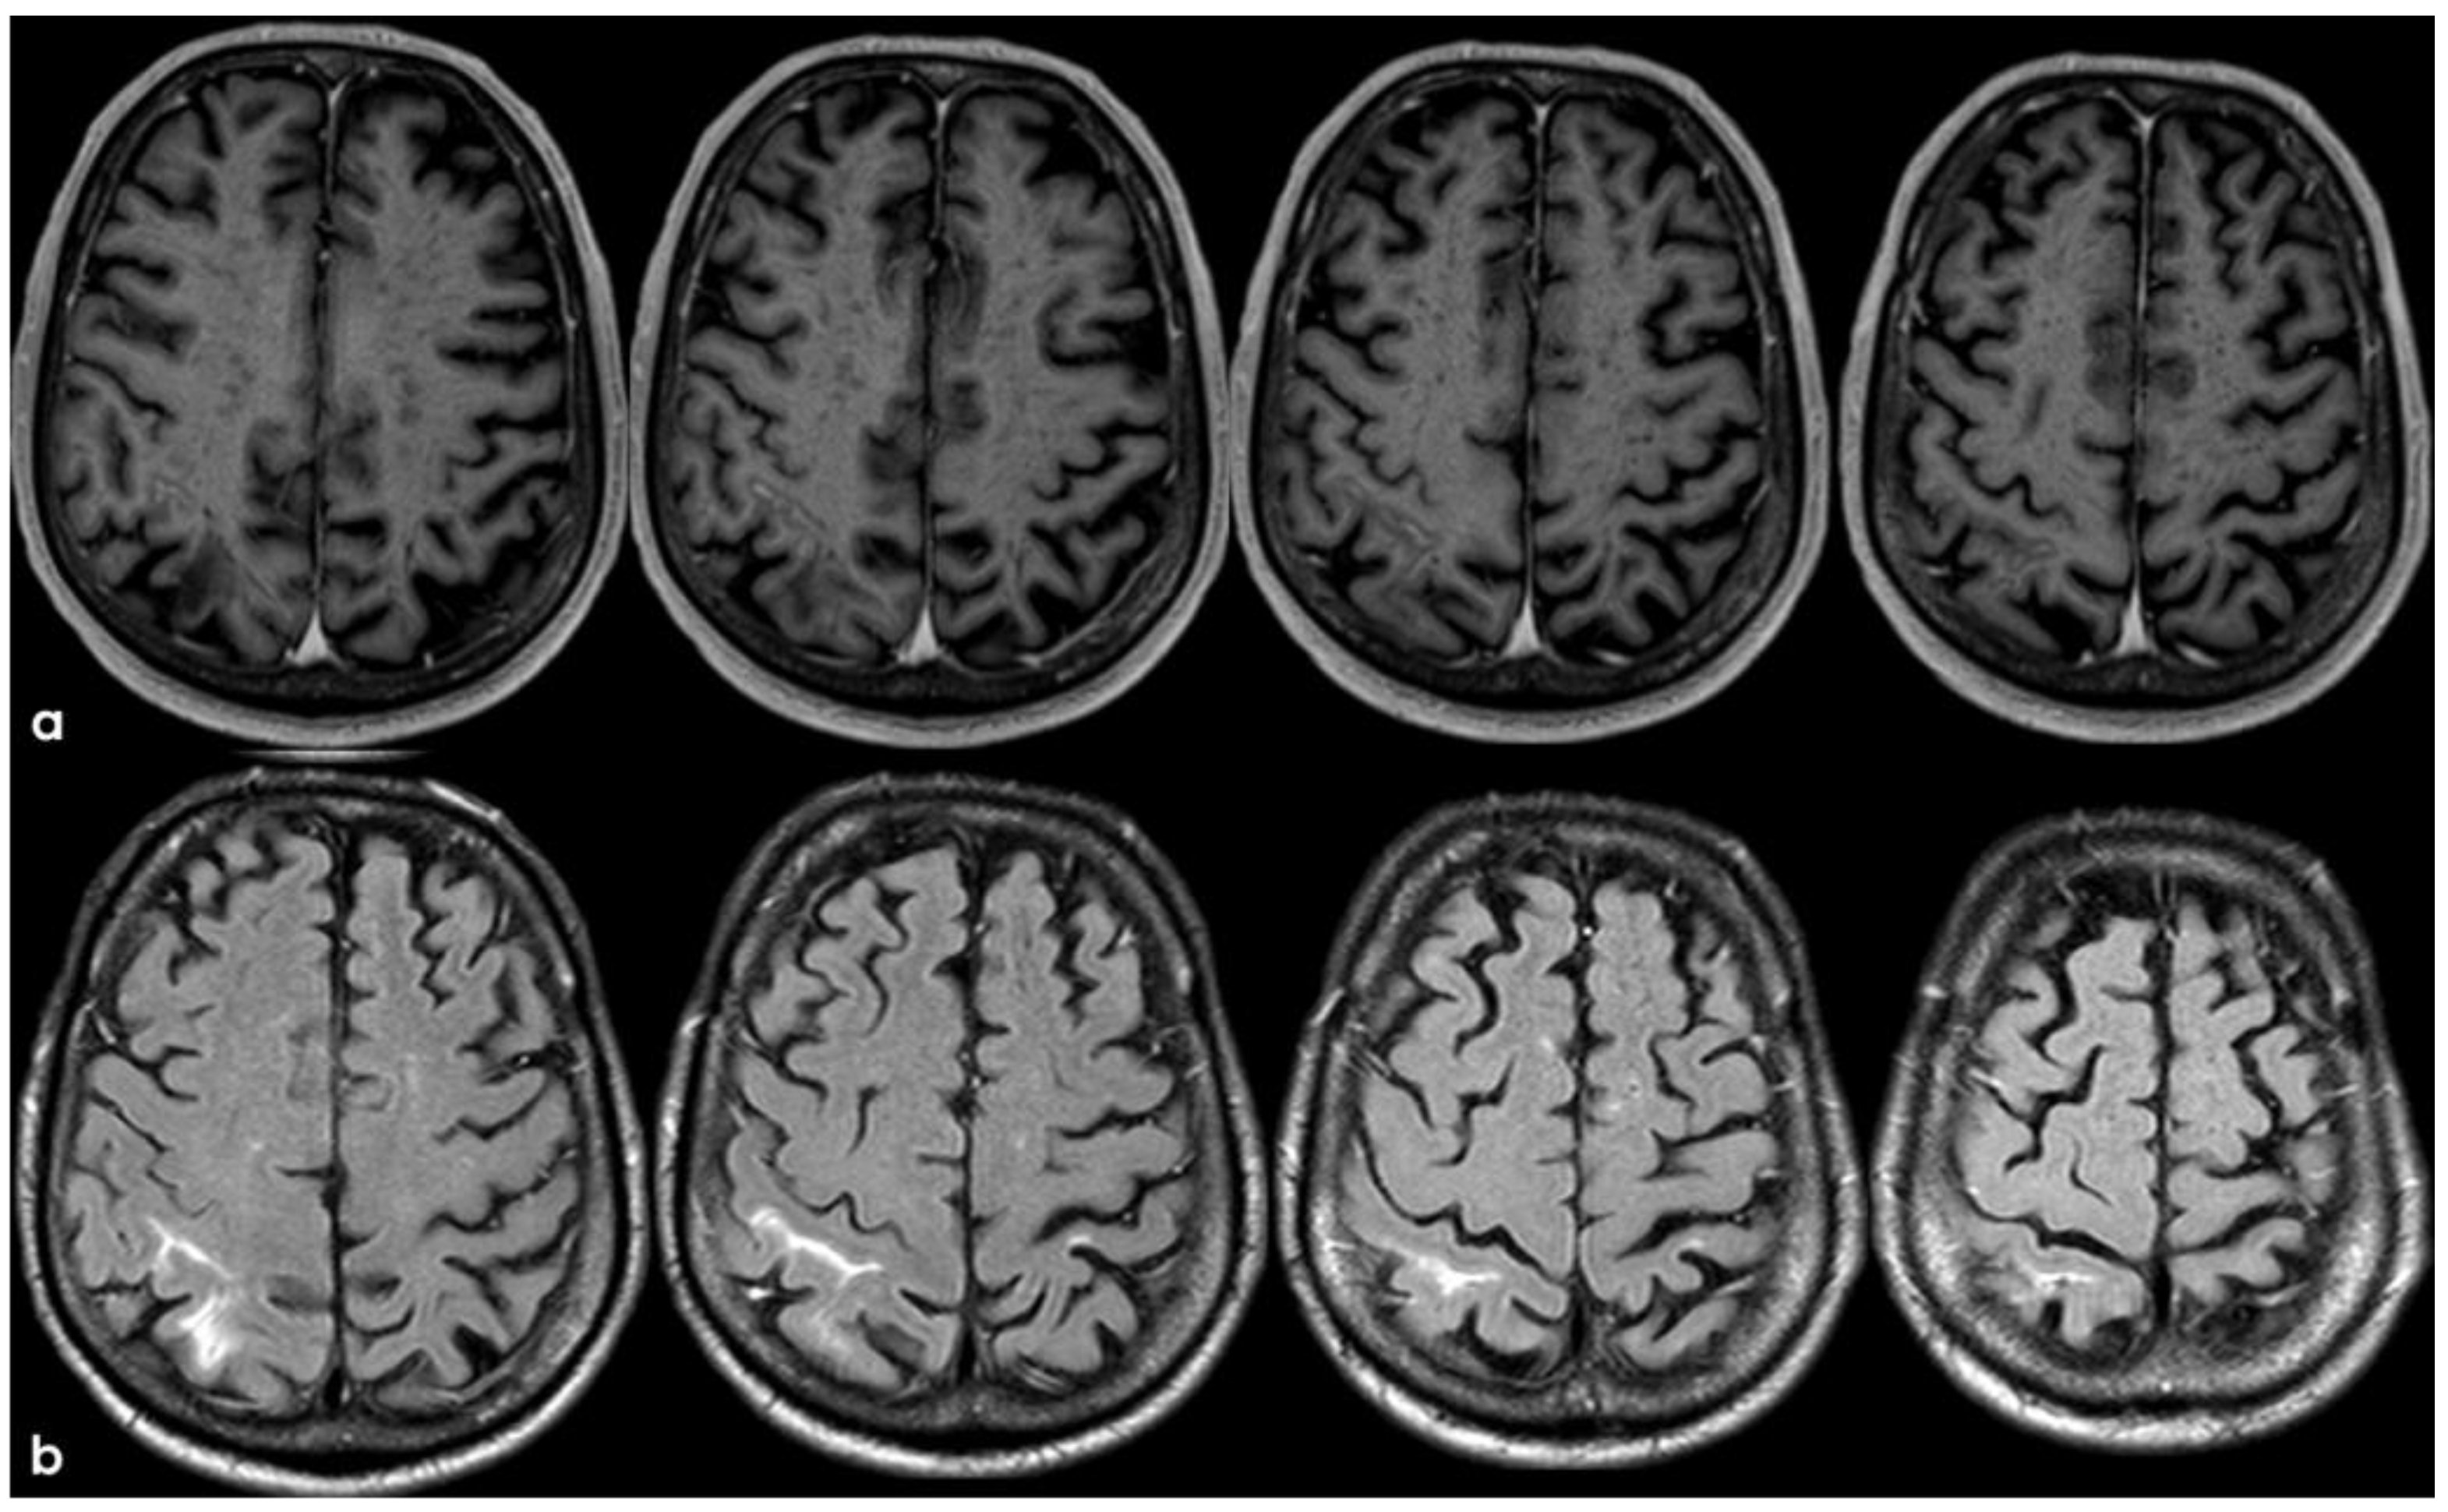

3. May 2014: CAA-Related Inflammation

5. February 2017: First Recurrent CAA-Related Inflammation

7. April 2018: Second Recurrent CAA-Related Inflammation